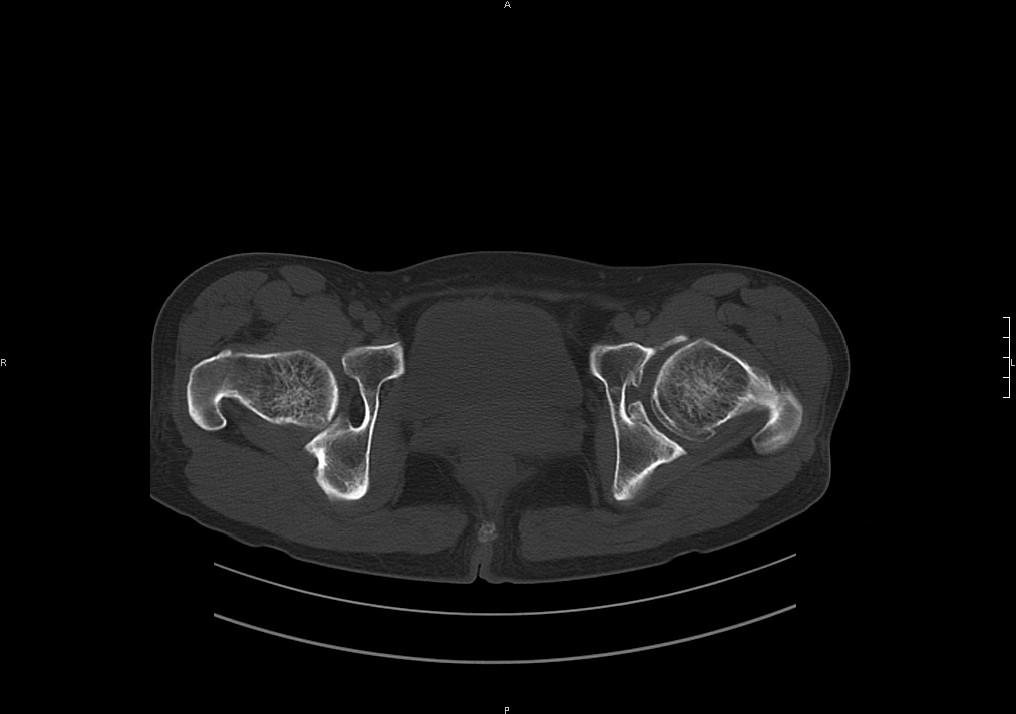

左髋关节内内可见关节鼠及滑囊积液.

考虑为滑膜骨软骨瘤病.

滑膜增厚钙化,关节鼠及滑囊积液,髋臼增生。考虑骨性关节病

髋臼平浅,股骨头覆盖率减小,考虑双侧髋关节发育不良伴退行性变。